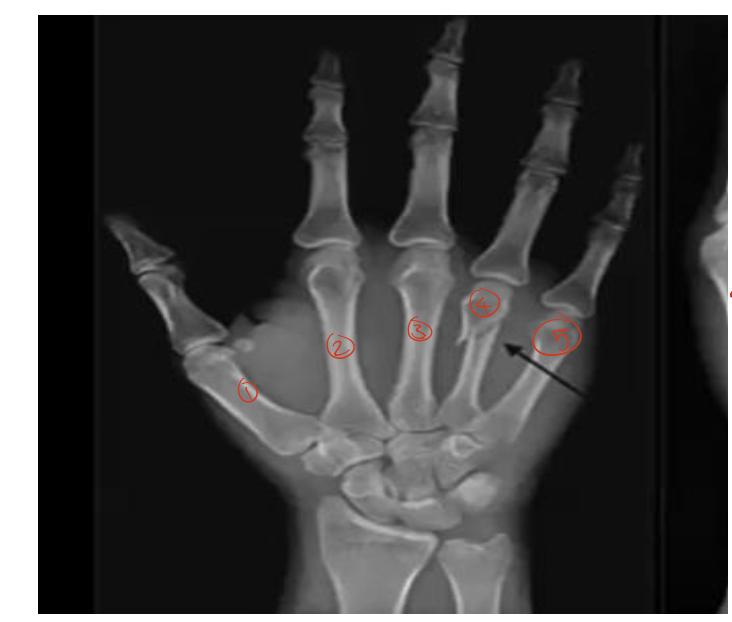

type of fracture ?

/

SAY everything